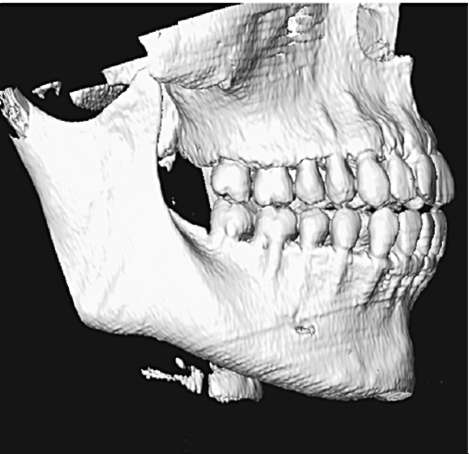

Исторически термин «биотип пародонта» введен С. Ochsenbein в 1969 г. На основании таких критериев, как высота и ширина коронок зубов, толщина альвеолярной кости и десны, а также величина зоны прикрепленной десны, им предложено выделять два биотипа пародонта: тонкий и толстый. Для тонкого биотипа характерны высокие и узкие коронки зубов, малая зона прикрепленной десны (рис. 4-7, см. цв. вклейку), множественные дигисценции (щелевидные дефекты альвеолярной кости с обнажением корня) и фенестрации корней (дефекты в виде окна). Толстому биотипу, как правило, свойственны короткие и широкие коронки зубов, большая зона прикрепленной десны (рис. 4-8, см. цв. вклейку), маргинальный костный контур массивный, фиброзный слой десны более выражен. Тонкий биотип пародонта встречается у 15% населения, толстый - у 85% соответственно. По данным М.Д. Петровой, средняя распространенность дигисценции корней (тонкого биотипа) составляет 20%.

В зависимости от биотипа пародонт по-разному реагирует на воспалительное повреждение, оперативное вмешательство и ортодонтическое лечение. Толщина вестибулярной костной пластинки определяет клиническое течение пародонтита. Воспалительная деструкция костной ткани - длительный процесс, развивающийся годами. Накопление таких провоспалительных факторов, как ИЛ-1 и фактор некроза опухоли-α (ФНО-α), способствует образованию остеокластов и усилению резорбции костной ткани. Естественно, скорость этой резорбции, приводящей к клиническим признакам пародонтита, напрямую зависит от объема костной ткани челюсти. Воспаление в костной ткани при развитии пародонтита в условиях толстого биотипа сопровождается образованием локальных пародонтальных карманов (рис. 4-9), резорбция альвеолярной кости и потеря клинического прикрепления при тонком биотипе проявляется в виде рецессий десны (рис. 4-10). Таким образом, при тонком биотипе пародонта с дефицитом костной ткани течение пародонтита носит более агрессивный характер вследствие ускоренной альтерации тканей. Прогноз лечения хронического пародонтита в данном случае менее благоприятный.

Рис. 4-10. Тонкий биотип